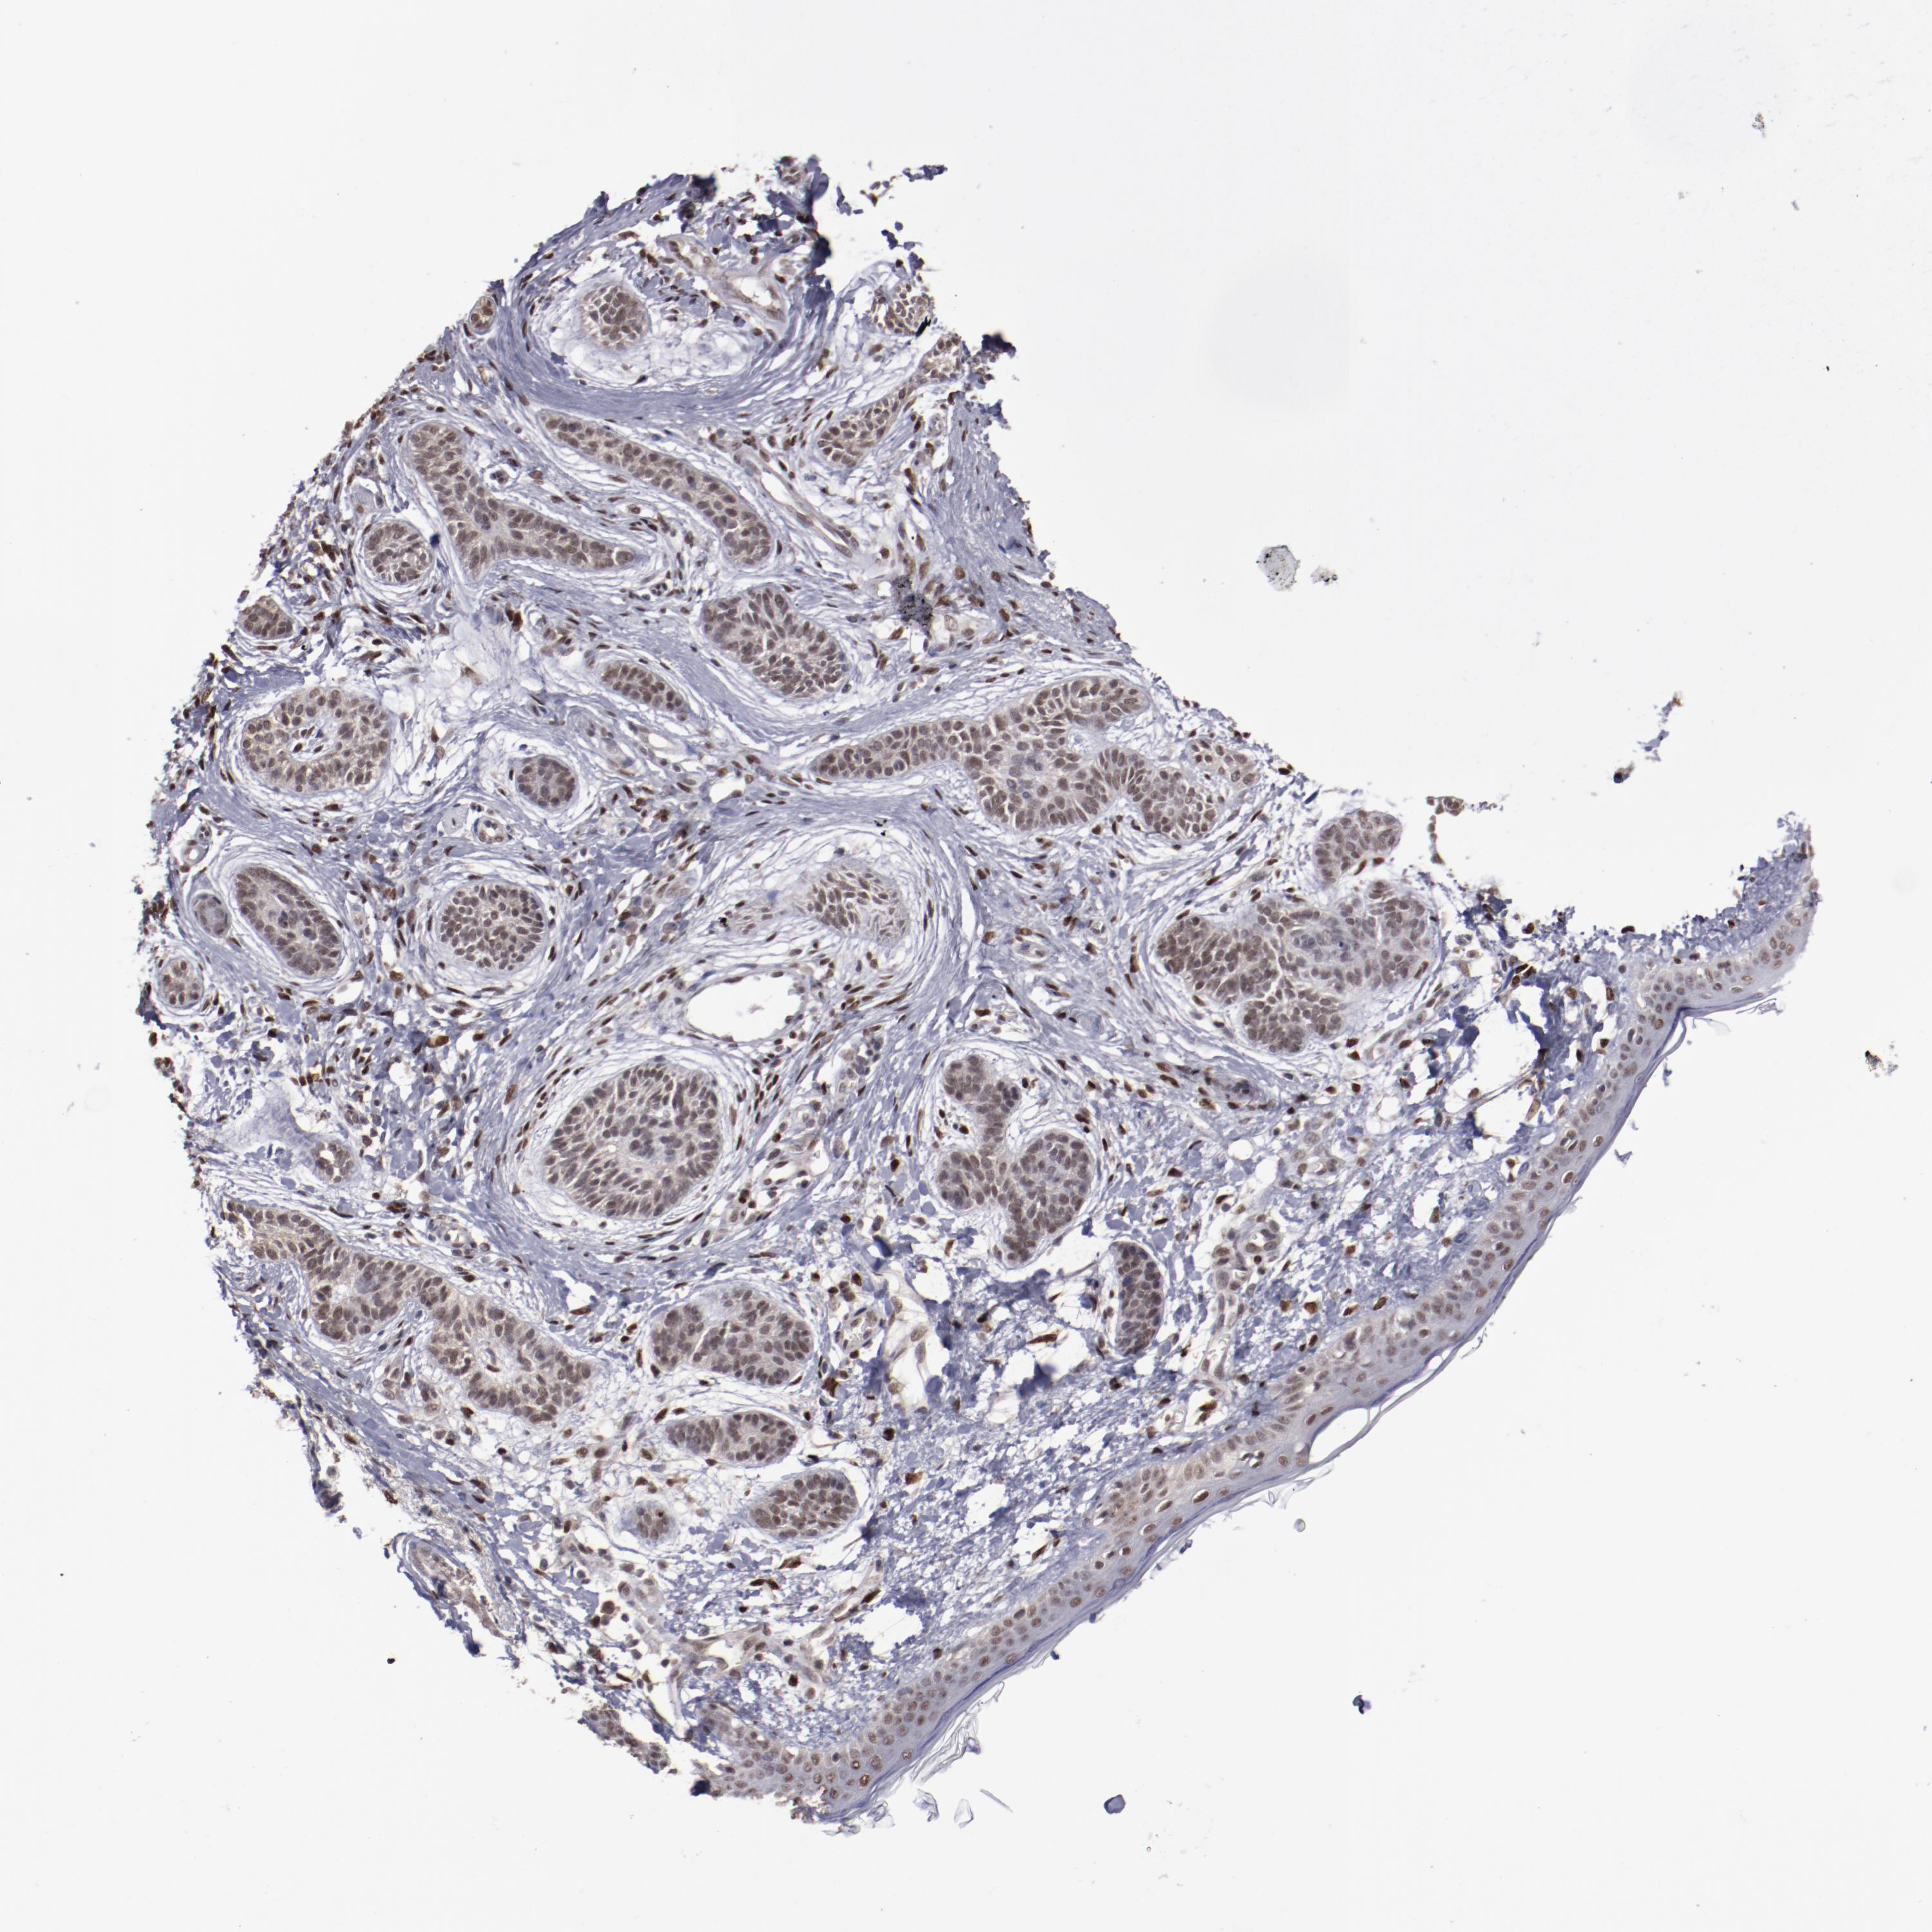

SKIN CANCER - Protein expressioni

A mouse-over function shows sample information and annotation data. Click on an image to view it in a full screen mode. Samples can be filtered based on level of antibody staining by selecting one or several of the following categories: high, medium, low and not detected. The assay and annotation is described here.

Antibody stainingi

Antibody staining in the annotated cell types in the current human tissue is reported as not detected, low, medium, or high, based on conventional immunohistochemistry profiling in selected tissues. This score is based on the combination of the staining intensity and fraction of stained cells.

Each image is clickable and will lead to virtual microscopy that enables deeper exploration of all samples and also displays staining intensity scores, fraction scores and subcellular localization as well as patient and tissue information for each sample.

Antibody CAB004318

Basal cell carcinoma